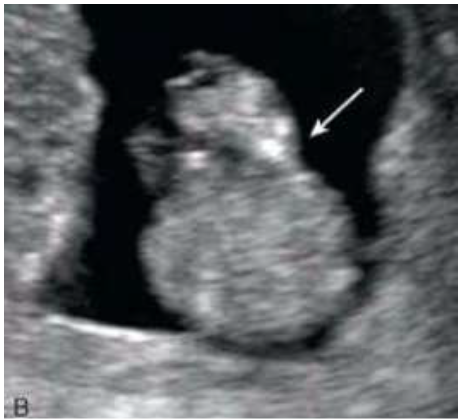

Paciente 24 anos, secundigesta, apresentando idade gestacional de 23 semanas, gestação não planejada, encaminhada para avaliação morfológica do segundo trimestre.

Após analisar as imagens abaixo, quais os sinais ecográficos encontrados e qual a hipótese diagnóstica?